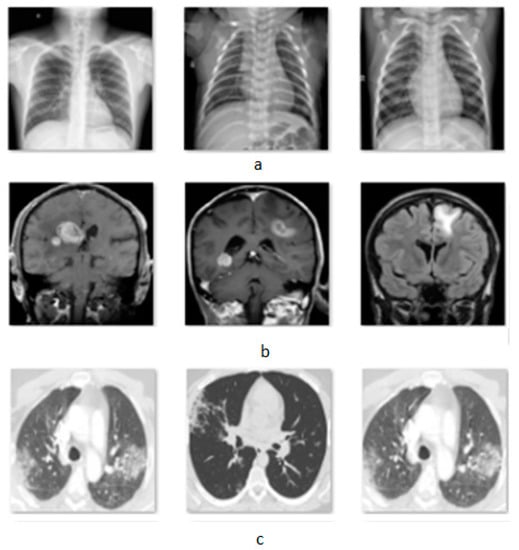

The attack was applied in classification problems in three different modalities. The first dataset [] is an X-ray set from the lungs that classifies the images into three categories, normal, pneumonia, and COVID-19, containing 3840 images. The second dataset [] consists of brain MRIs of four tumor categories with 3264 total images and the last dataset [] is a binary classification of CT-Scans for COVID-19 and non-COVID-19 lungs, providing 2481 images. In Figure 2 is presented a sample of the used datasets.

Figure 2.

Images from three datasets, (a) X-rays, (b) MRIs, and (c) CT-Scans.